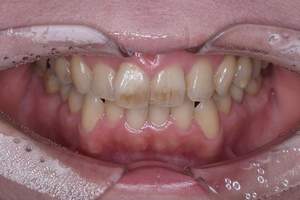

歯石除去

治療前

治療後

| 年齢 | 25歳・男性 |

| 主訴 | 歯石をとりたい・検診 |

| 治療内容 | 各種検査・歯石除去 |

| 治療期間 | 60分 |

| 費用 | 初診料3,000〜4,000円前後 +歯石除去約1,000円 |

| リスク・副作用 | ・処置後に歯がしみることがあります。 ・歯と歯の間に隙間ができるので、息が漏れ発音しにくいと感じることがあります。 ・歯ぐきの炎症が軽減すると歯ぐきが引き締まり、歯が長く見えることがあります。 |

| 担当者所見 | 前歯の裏側にすぐに歯石が溜まってしまいザラザラして気になるとご相談いただいたので適切な歯ブラシの当て方とフロスの通し方をお伝えさせて頂きました。 |